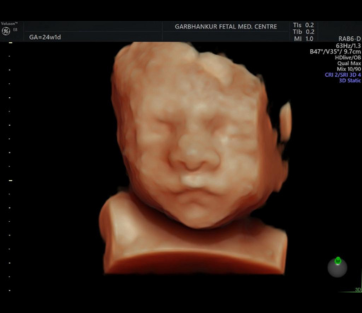

3D/4D

3D and 4D ultrasound are advanced imaging techniques use sound waves to create three-dimensional(3D) images or moving real-time 3D images(4D) of the developing baby

- Purpose

- Procedure

- Detection of Cardiac Abnormalities

- Follow-Up and Management

- Importance